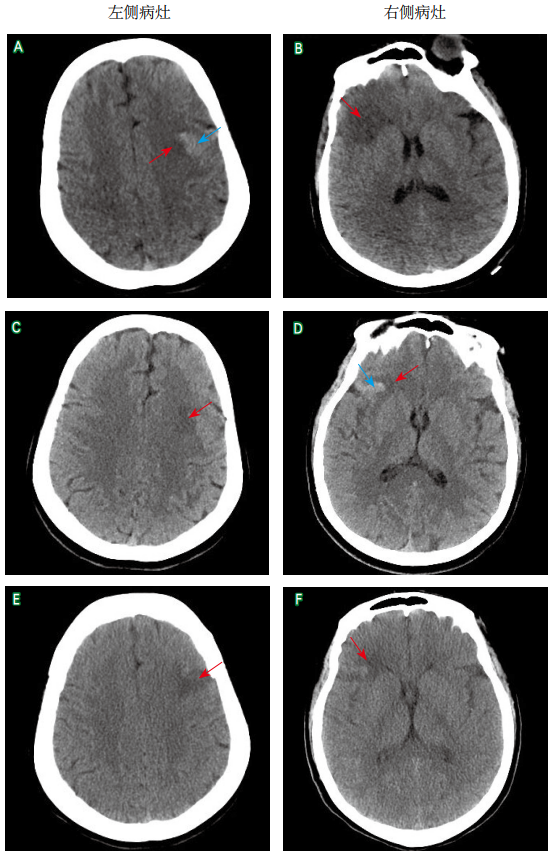

伴皮质下梗死和白质脑病的常染色体显性遗传性脑动脉病患者大脑中动脉闭塞血管内治疗1例并文献复习

摘要:伴皮质下梗死和白质脑病的常染色体显性遗传性脑动脉病(cerebral autosomal dominant arteriopathy with subcortical infarcts and leukoencephalopathy,CADASIL)是NOTCH3基因突变所致的遗传性脑小血管病,主要病变血管为颅内小动脉,累及大脑皮质和颅内大/中动脉的报道较罕见,目前缺乏特效治疗方法。本文报道